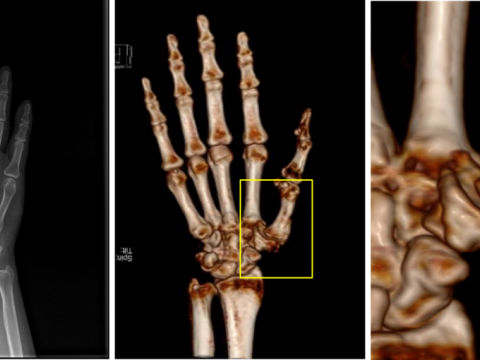

- 多人摔伤致粉碎性骨折 西南医大中医院3D打印术助其快速恢复

- 3D打印多孔钽金属掌指关节置换成功实施

- 安医大一附院首次自主开展3D打印技术应用于手术治疗